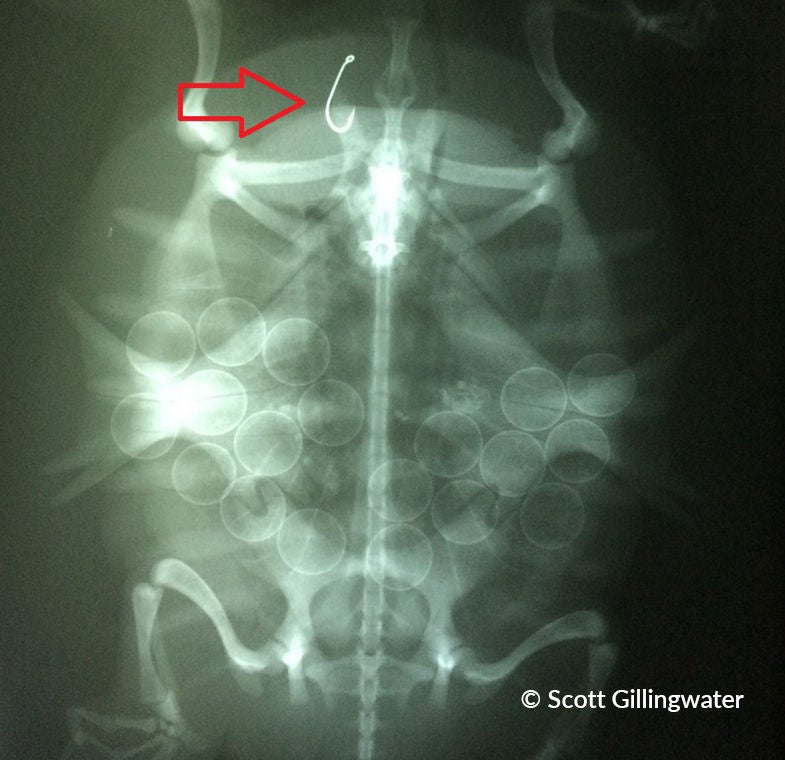

Tortue serpentine avec hameçon dans la bouche

Certains hameçons restent pris dans la bouche de la tortue, ce qui nuit à sa capacité de s’alimenter. D’autres hameçons sont avalés et demeurent logés dans la gorge ou l’estomac, ce qui peut être mortel. Même si ce n’est pas l’hameçon qui tue la tortue, elle peut mourir d’intoxication au plomb si elle avale aussi le plomb.

Les études démontrent que l’hameçonnage accidentel de tortues est courant et répandu. Les tortues serpentines sont l’espèce la plus souvent hameçonnée, sûrement en raison de leur taille, leur aire de répartition élargie et leurs habitudes d’alimentation. D’autres espèces qui se font souvent hameçonner sont la tortue géographique, la tortue peinte, la tortue-molle à épines et la tortue des bois.